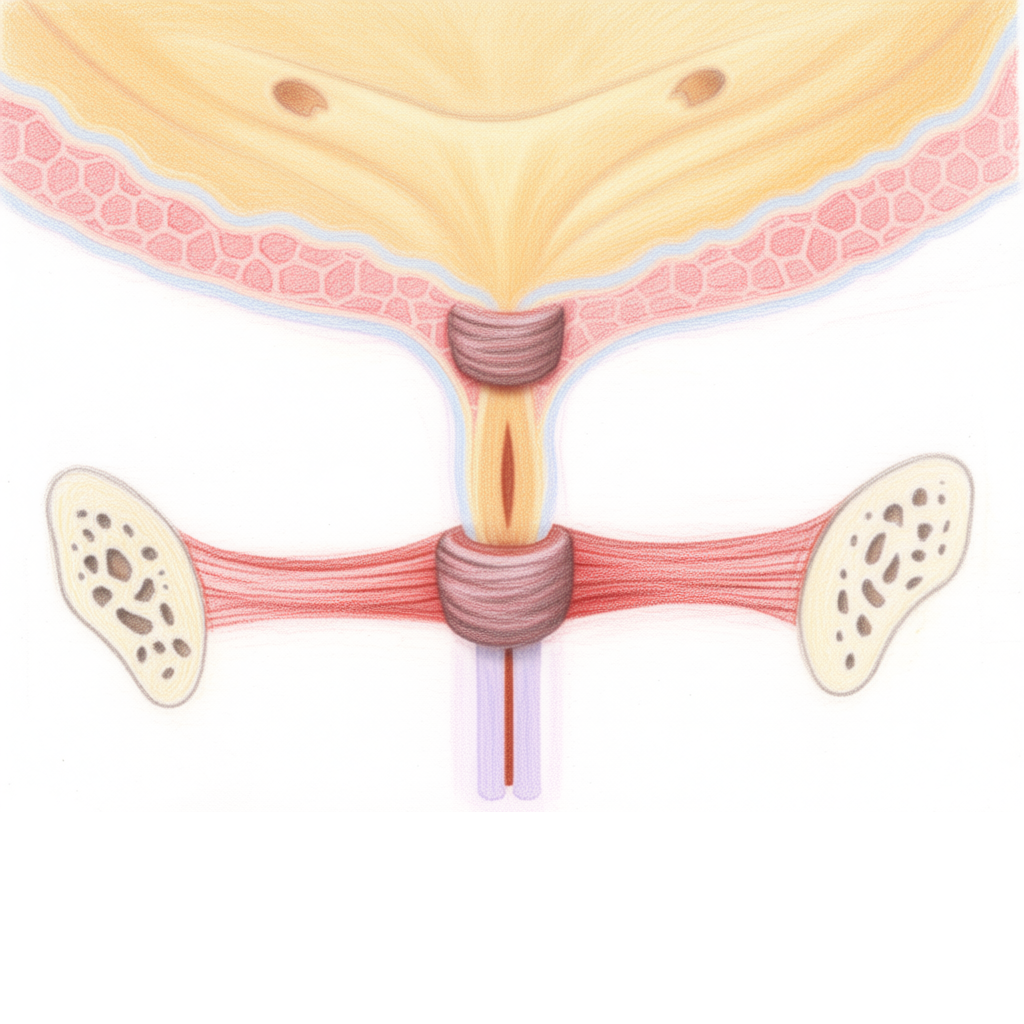

PRED:

Oslabené svaly močovej rúry

PO:

Posilnené svaly močovej rúry